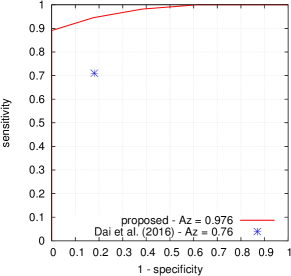

FROC curves are reported in Fig. 6 for ‘net B’; areas under the limited FROC curve for all three ConvNets are summarized in Table 3. It appears that the number of false alarms is rather large, particularly in the case of microaneurysm detection. The reason is that human experts primarily segmented the most obvious lesions, while screening algorithms need to focus on the most subtle lesions as well. In other words, many true lesions are counted as false alarms. Of course, this comment also applies to competing automatic solutions. To show the value of our detections, the proposed solution was compared in Fig. 7 to results reported in the literature, following the DiaretDB1 standardized procedure (see section 5.3.2). Most authors reported a single (sensitivity, specificity) pair: this is what we reported in Fig. 7. Some authors reported ROC curves; in that case, we also reported a single (sensitivity, specificity) pair: the one closest to the (sensitivity = 1, specificity = 1) coordinate. Note that all competing solutions (Kauppi et al., 2007; Yang et al., 2013; Franklin and Rajan, 2014; Kumar et al., 2014; Bharali et al., 2015; Mane et al., 2015; Dai et al., 2016) are trained at the lesion level, while ours is trained (in Kaggle-train) at the image level.

Three ConvNets were trained to detect referable DR in the Kaggle-train dataset, using the proposed heatmap optimization procedure. Then, we evaluated how well those ConvNets could detect lesions in the DiaretDB1 dataset, without retraining them. For lesion detection at the image level, they outperformed previous algorithms, which were explicitly trained to detect the target lesions, with pixel-level supervision (see Fig. 7). This superiority was observed for all lesions or groups of lesions, with the exception of ‘red lesions’. Experiments were also performed at the lesion level: for all lesion types, the proposed algorithm was found to outperform recent heatmap generation algorithms (see Table 3). As illustrated in two examples (see Fig. 9 and 10), the produced heatmaps are of very good quality. In particular, the false alarms detected on the vessels, in the vicinity of true lesions in the unoptimized heatmaps ( maps), are strongly reduced with sparsity maximization (, , ). These experiments validate the relevance of image-level supervision for lesion detectors, but stress the need to optimize the heatmaps, as proposed in this paper. Note that detection performance is not affected much by image quality: very good detections are produced in the blurry image obtained with a low-cost, handheld retinograph (see Fig. 10). This is a very important feature, which opens the way to automated mobile screening. However, it can be observed that the ‘AlexNet’ architecture, which achieves moderate DR detection results, also achieves poor detection results at the lesion level, even after heatmap optimization (see Table 3): to ensure good detection performance at the lesion level, the proposed optimization framework should be applied to ConvNet architectures that achieve good image-level performance.